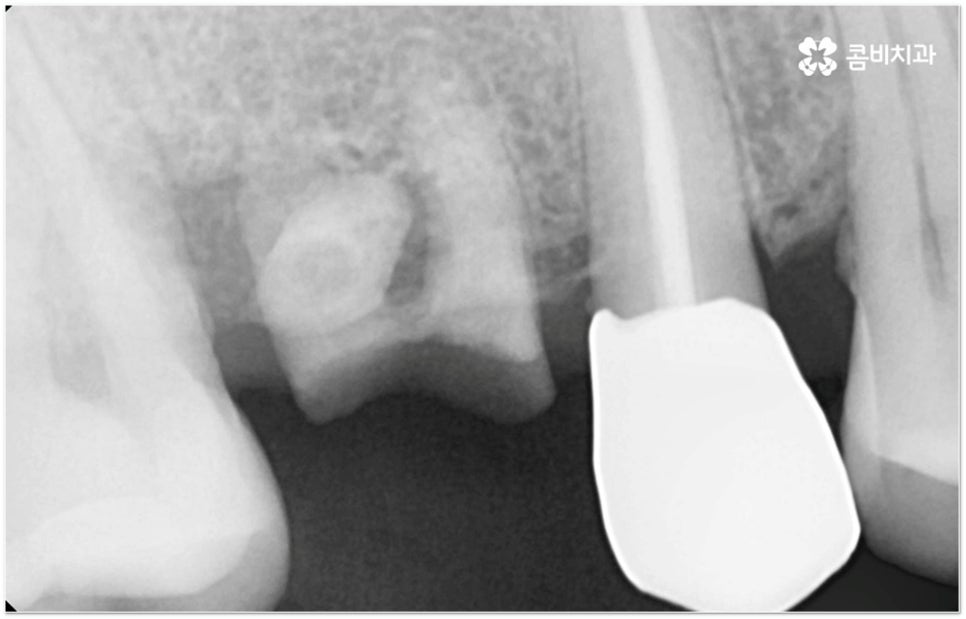

그러나 임플란트는 잇몸뼈에 직접 심어서 고정시키는 방식인 만큼 만약 환자분의 잇몸뼈가 부족하거나 치아가 빠진 후 오랜 시간이 지나 이미 잇몸뼈 소실이 상당 부분 이루어진 상태라고 한다면 먼저 골이식을 통해 이를 보충한 후 식립을 진행하는 뼈이식임플란트 방식을 이용할 필요가 있어요. 골이식 과정은 바탕이 되는 잇몸뼈의 밀도나 높이, 두께가 부족한 부분에 이식 재료를 심어주어 뼈를 재건해 주는 것인데 충분한 시간을 두고 무리하지 않게 진행하는 것이 뼈이식임플란트 수술의 성공률 및 안정적인 지속성을 높일 수 있는 방법이 될 거예요.

뼈이식임플란트 가 필요한지 살펴볼 때 3D CT 촬영과 같은 정밀 진단을 통해서 환자분의 잇몸뼈 두께 등 치조골 상태 뿐 만 아니라 구강 구조, 치아 및 잇몸 상태, 신경관 위치, 상악동까지의 거리 등을 꼼꼼하게 확인하여 치료 계획을 세우고 필요하다면 구강 질환에 대한 치료나 상악동 거상술 등을 선행하며 잇몸뼈 부족에 대해서도 골이식 과정을 먼저 진행하게 되는데요, 이러한 뼈이식임플란트 시술은 상당히 고난도의 복잡한 치과 진료인 만큼 관련 임상 경험이 풍부한 의료진과 함께 하는 것이 굉장히 중요하며 또한 수술 후 관리 면에서도 더욱 신경을 써 주시길 당부드리고 있어요.